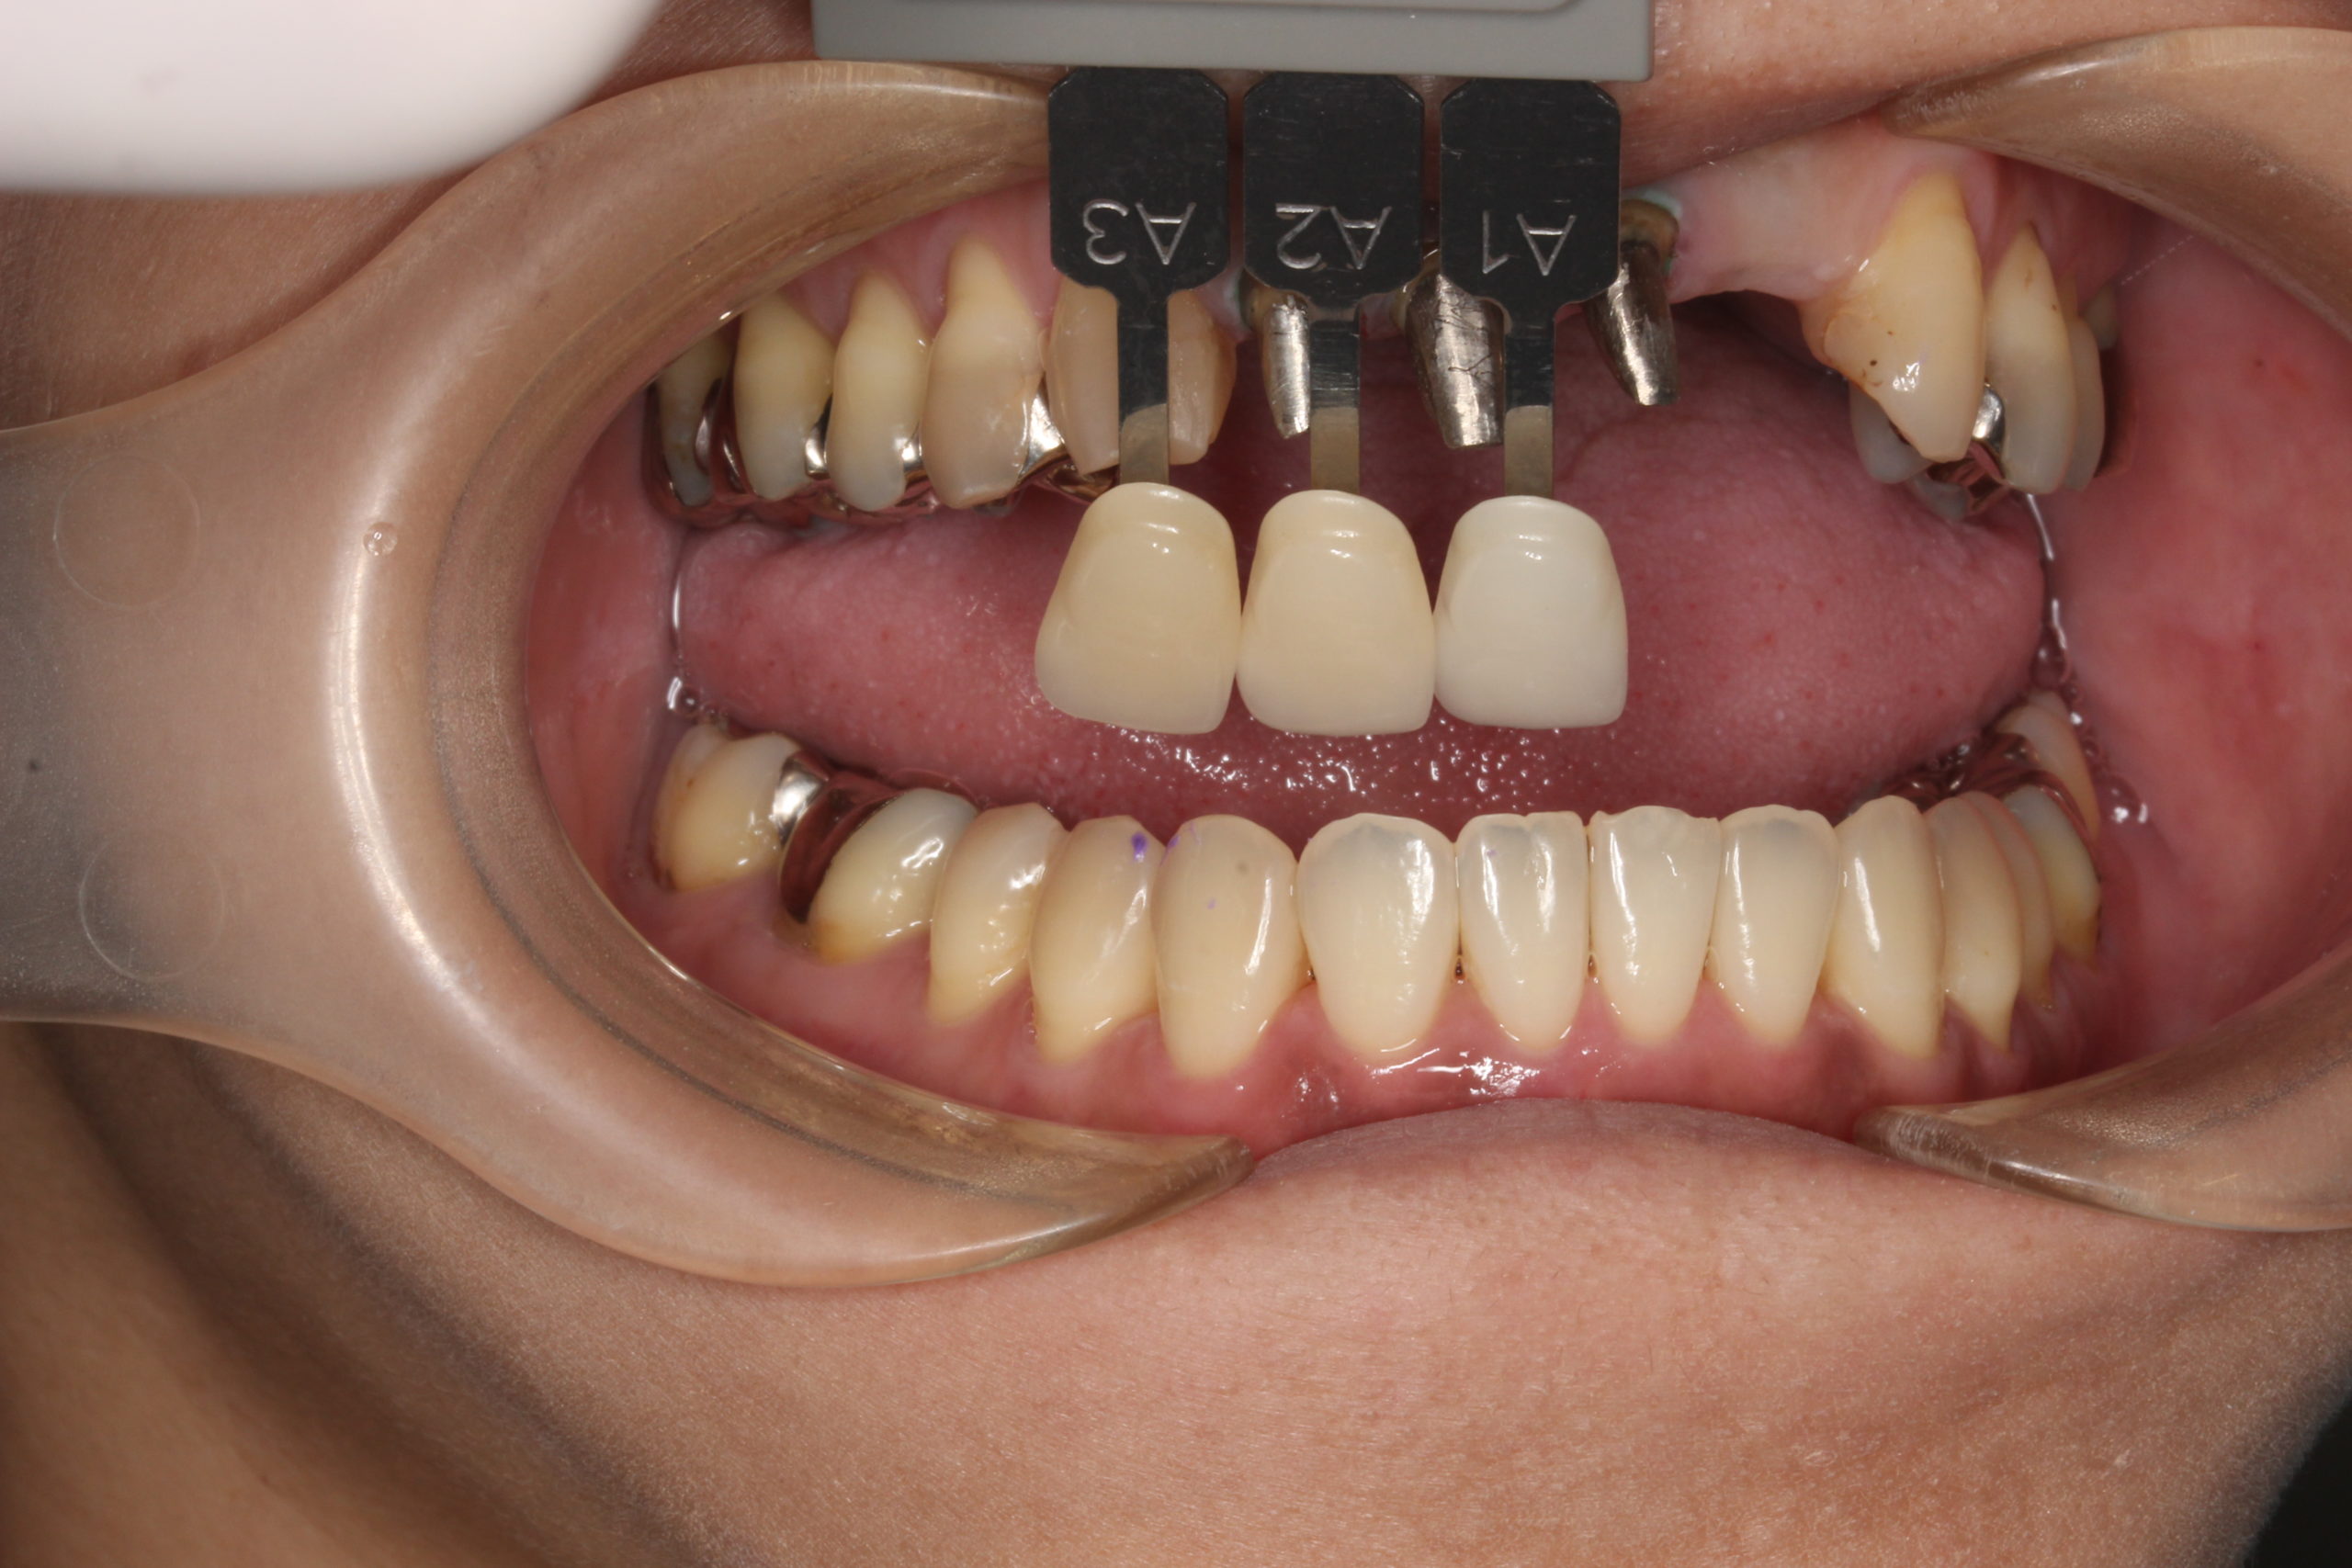

審美歯科

前の歯医者では治療がなかなか進まない…銀歯もセラミックに交換して審美歯科

全ての銀歯を白く綺麗に治す。